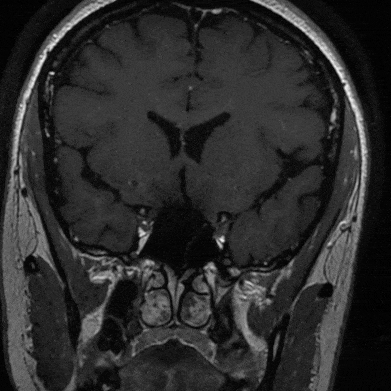

入院后查高分辨核磁显示:左侧颈内动脉交通段、左侧大脑前动脉A1段及左侧大脑中动脉M1段管壁明显强化,左侧颈内动脉交通段及左侧大脑中动脉M1段管腔内可见强化内膜片影,考虑左侧颈内动脉交通段夹层动脉瘤累及M1、A1段(左侧颈内动脉交通段及左侧大脑中动脉M1段管腔扩张,左侧大脑前动脉A1管腔明显狭窄)。